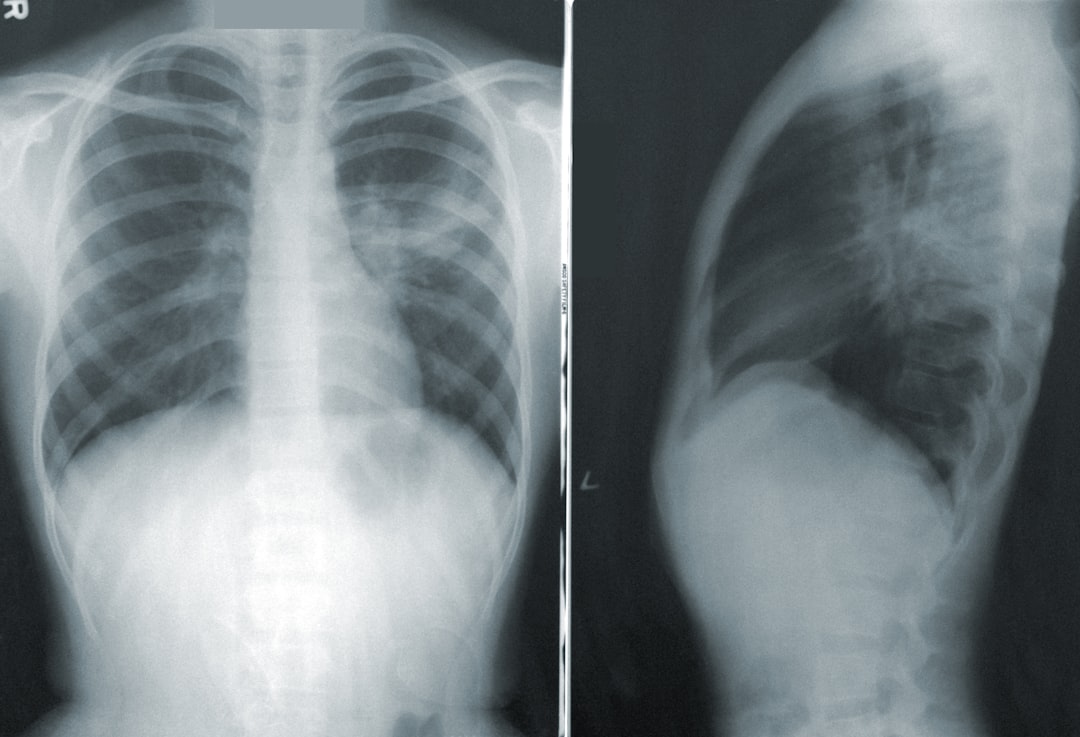

조기 발견과 적절한 치료가 중요한 만큼, 정기적인 검진이 필요합니다. 간단한 심전도 검사로 심방세동을 진단할 수 있으며, 심장 전문가와 상담하여 최적의 치료 방법을 찾는 것이 중요합니다. 다음에는 최신 치료 동향과 기술에 대해 더 깊이 들어가 보겠습니다!